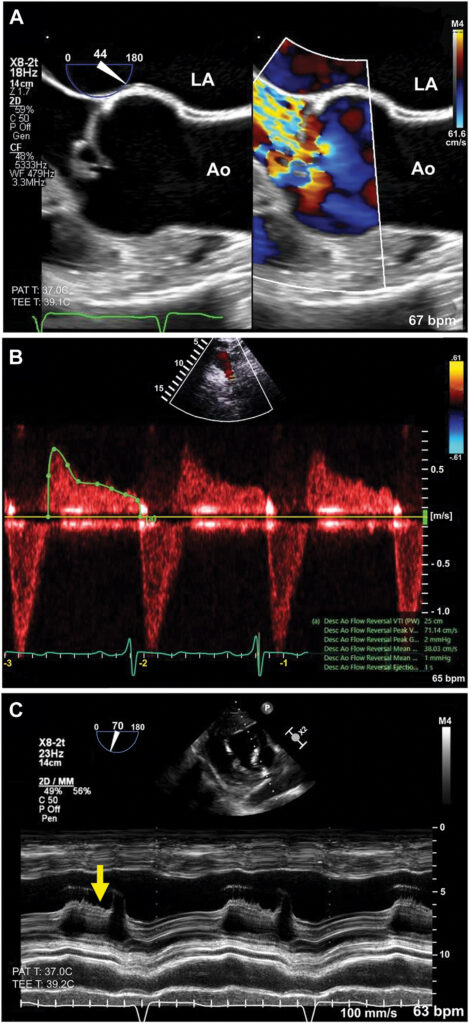

Ao exame, pressão arterial de 159×68 mmHg, abafamento de B1 e sopro holodiastólico (3/4+) mais audível no foco aórtico. Ecocardiograma mostrou uma valva aórtica trivalvular e um aparente prolapso do folheto coronariano direito, de elevada mobilidade, levando a considerar a possibilidade de flail. Ainda, havia uma regurgitação valvar significativa, com direção posterior, fluxo reverso holodiastólico em aorta descendente com VTI de 25 cm e dilatação da raiz aórtica (4,9 cm).

Também foi observado fechamento precoce da valva mitral, dilatação do ventrículo esquerdo (VE), com volume diastólico final indexado de 145 ml/m², hipertrofia concêntrica do VE importante (septo 17 mm, índice de massa 210 g/m² e espessura relativa 0.54), fração de ejeção 65%, porém com strain global longitudinal (SGL) reduzido (14%).

A IAo importante foi confirmada: volume regurgitante 76 mL, fração regurgitante de 61%, fluxo reverso holodiastólico em aorta abdominal, “flutter” (ver foto) no folheto anterior da valva mitral causando restrição de mobilidade.